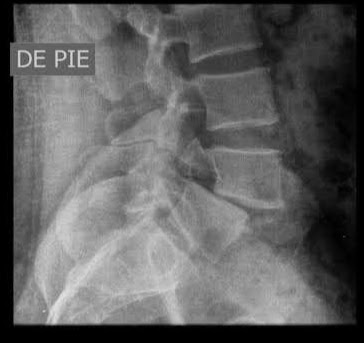

Name of condition seen in these images

https://photos.app.goo.gl/4TzEWbHzctdffqT1A

What is a lumbarization of S1?